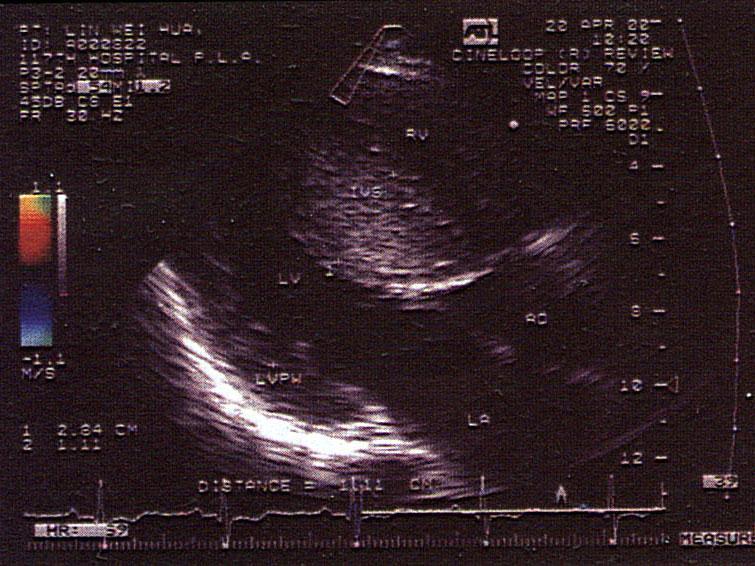

问题 该病例最可能的诊断?(?)

选项 A.高血压病 B.肥厚型心肌病 C.主动脉瓣狭窄 D.肌型主动脉瓣瓣下狭窄 E.限制性心肌病

答案 B